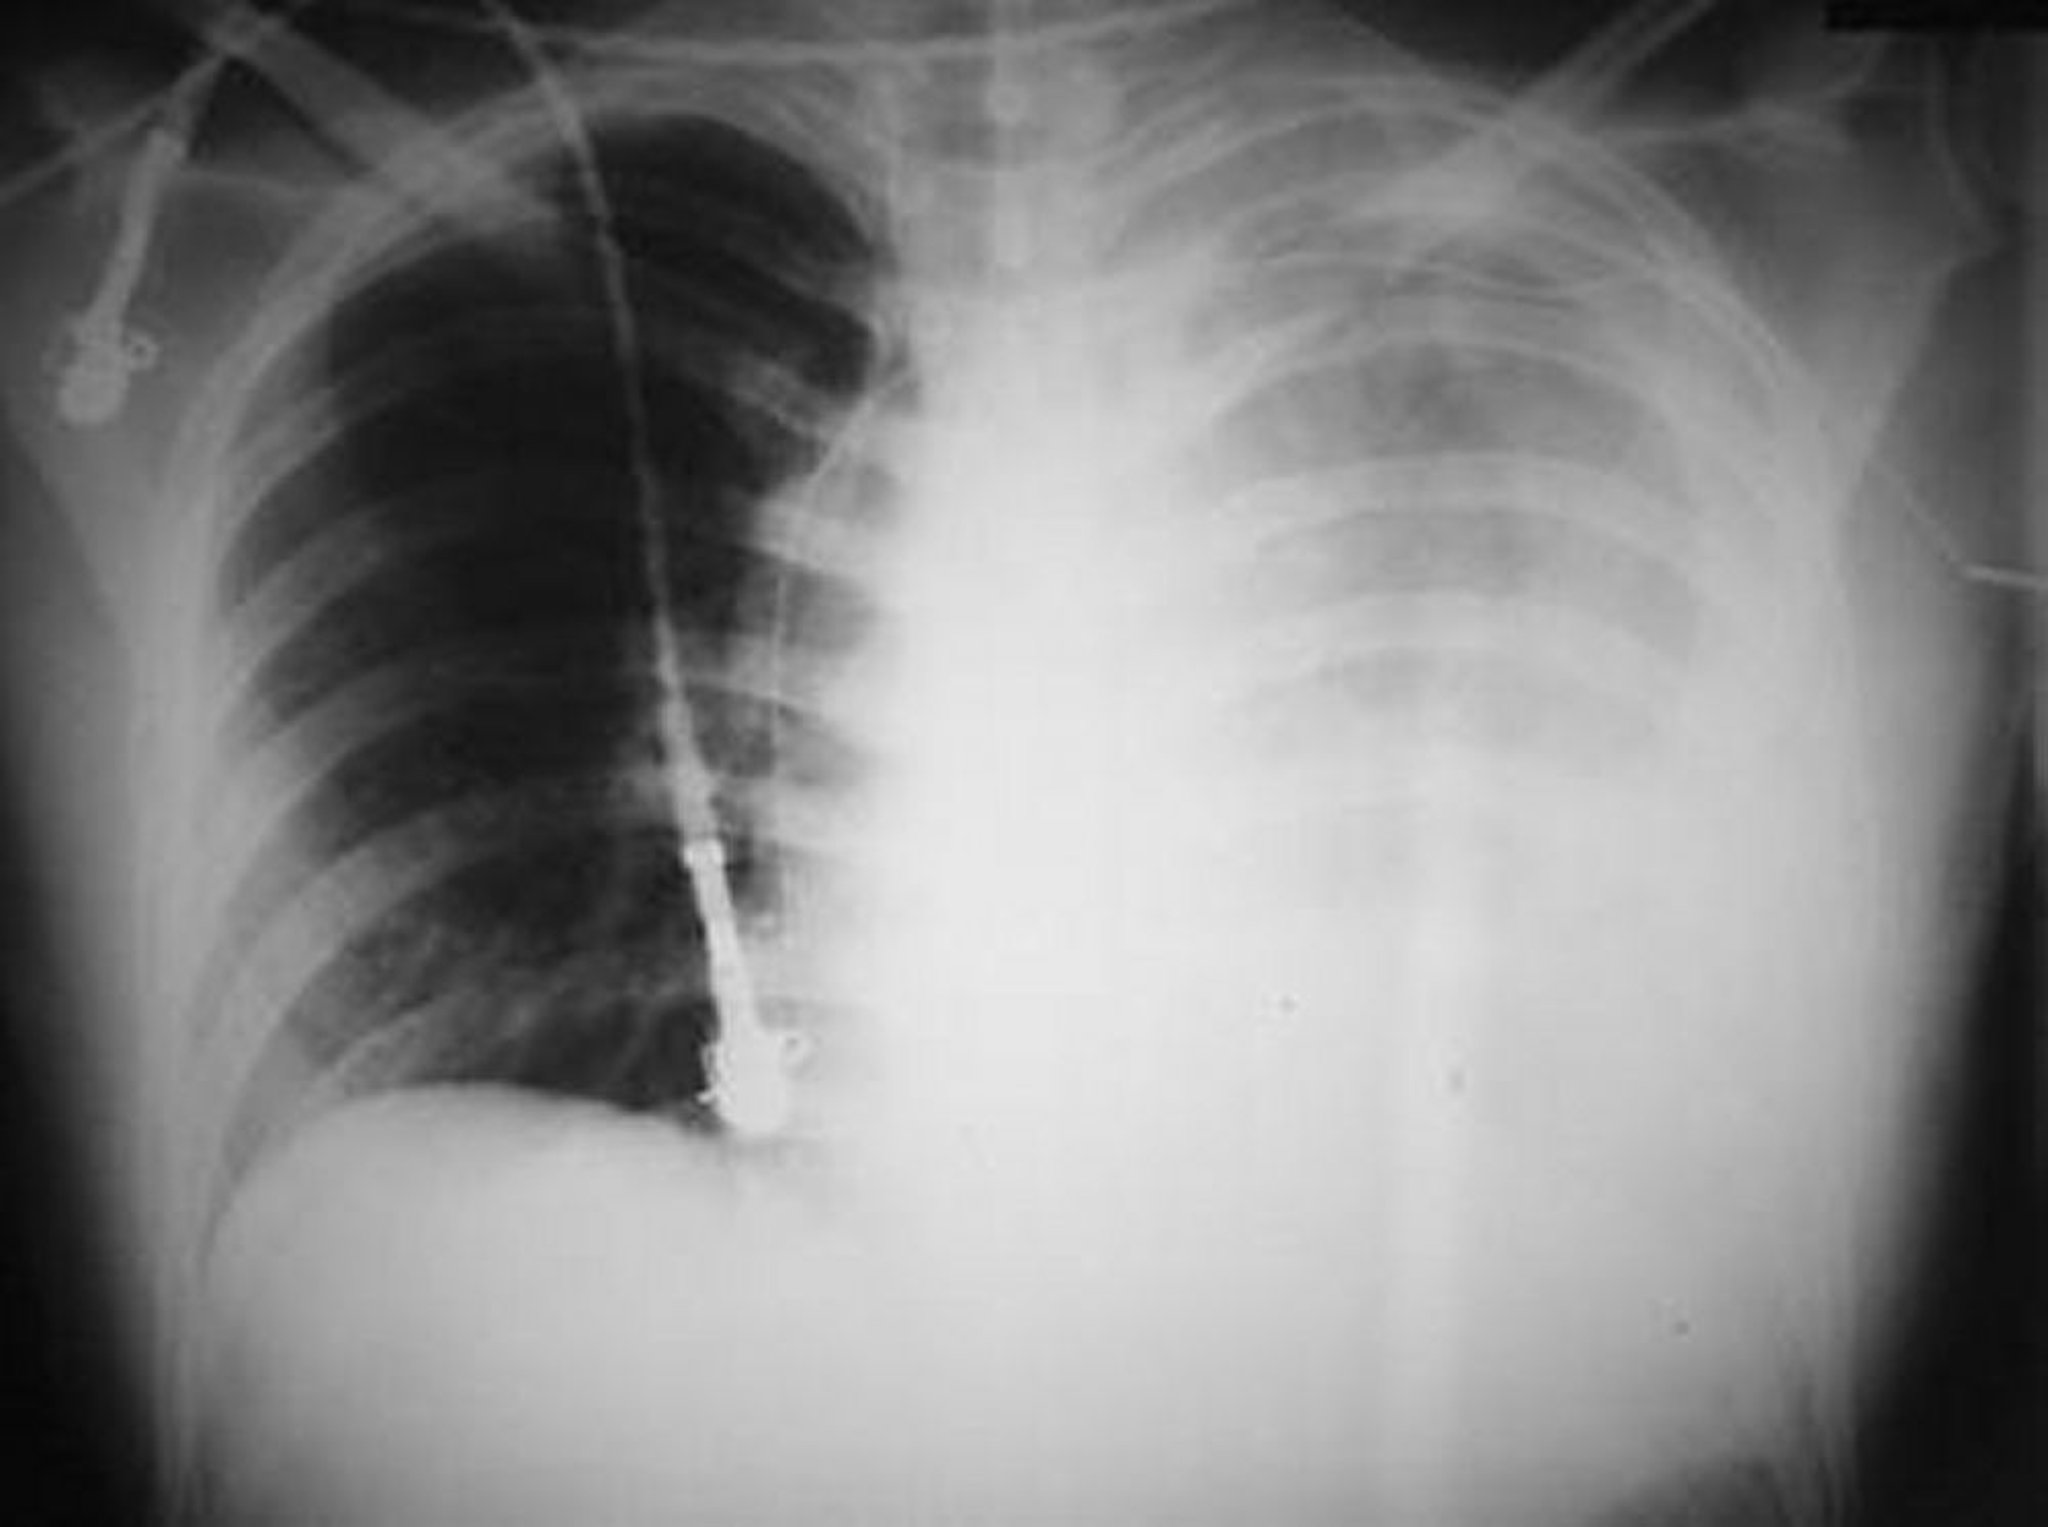

Questa foto mostra un emotorace sinistro massiccio in seguito ad una ferita da arma da fuoco alla parte sinistra del torace.

© Springer Science+Business Media